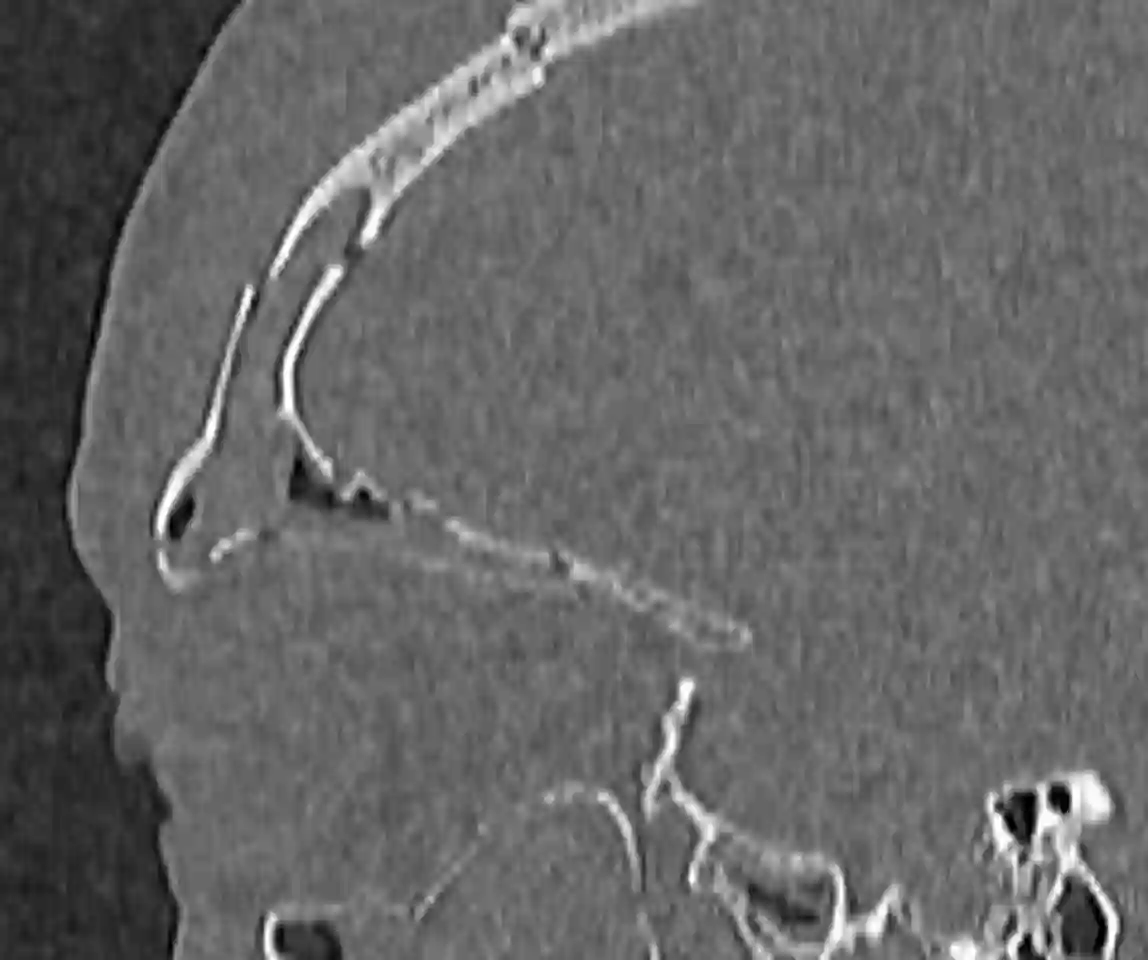

Sagittales CT Bild einer traumatischen Sinus frontalis Fraktur mit Beteiligung der Vorder- als auch Hinterwand.